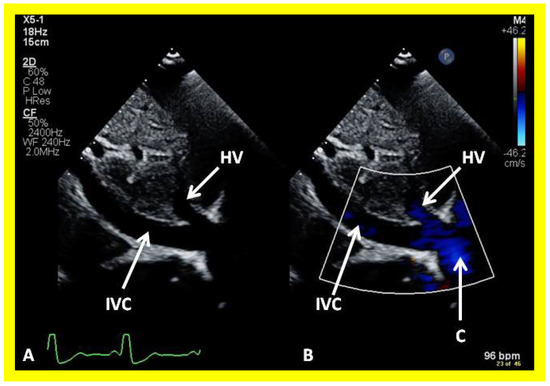

Cross-sectional views of the Fontan conduit were shown in Figure 38, Figure 39 and Figure 40. Imaging of the conduit longitudinally is also possible (Figure 46) and laminar flow in the conduit (Figure 46B) is indicative of a nonobstructive conduit. The connection between the IVC and the conduit (Figure 47 and Figure 48) can also be demonstrated by echo studies. Doppler interrogation demonstrating low flow velocities across this region (Figure 49) is indicative of nonobstructive IVC–conduit junction. Turbulent flow and high Doppler velocity across this region suggest obstruction; however, this is rarely seen.

Figure 42. Selected video frames from an apical view demonstrating laminar flow from the left ventricle into the aorta (Ao). Note laminar flow in the LV outflow tract (LVOT) and low Doppler flow velocity (~0.8 m/s).

Applsci 11 09472 g042